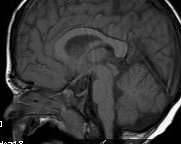

▼Jameson患有亚伯氏症 (Apert syndrome),这是一种罕见的先天性疾病。他的颅缝早期闭合,眼球突出,眼距过宽,还有其他身体畸形。这种病大多是新突变造成,患病的人还可能伴随有耳朵感染、水脑症等等可怕的疾病。